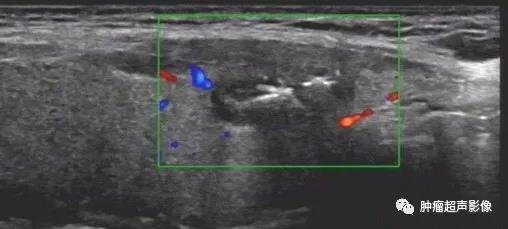

甲状腺结节呈低回声,局部边缘欠光整,内见粗钙化,可分到4类,内部无血流,

回顾以前检查可发现同一位置有一囊实性结节(下图),从而确诊皱缩结节,避免穿刺及手术。